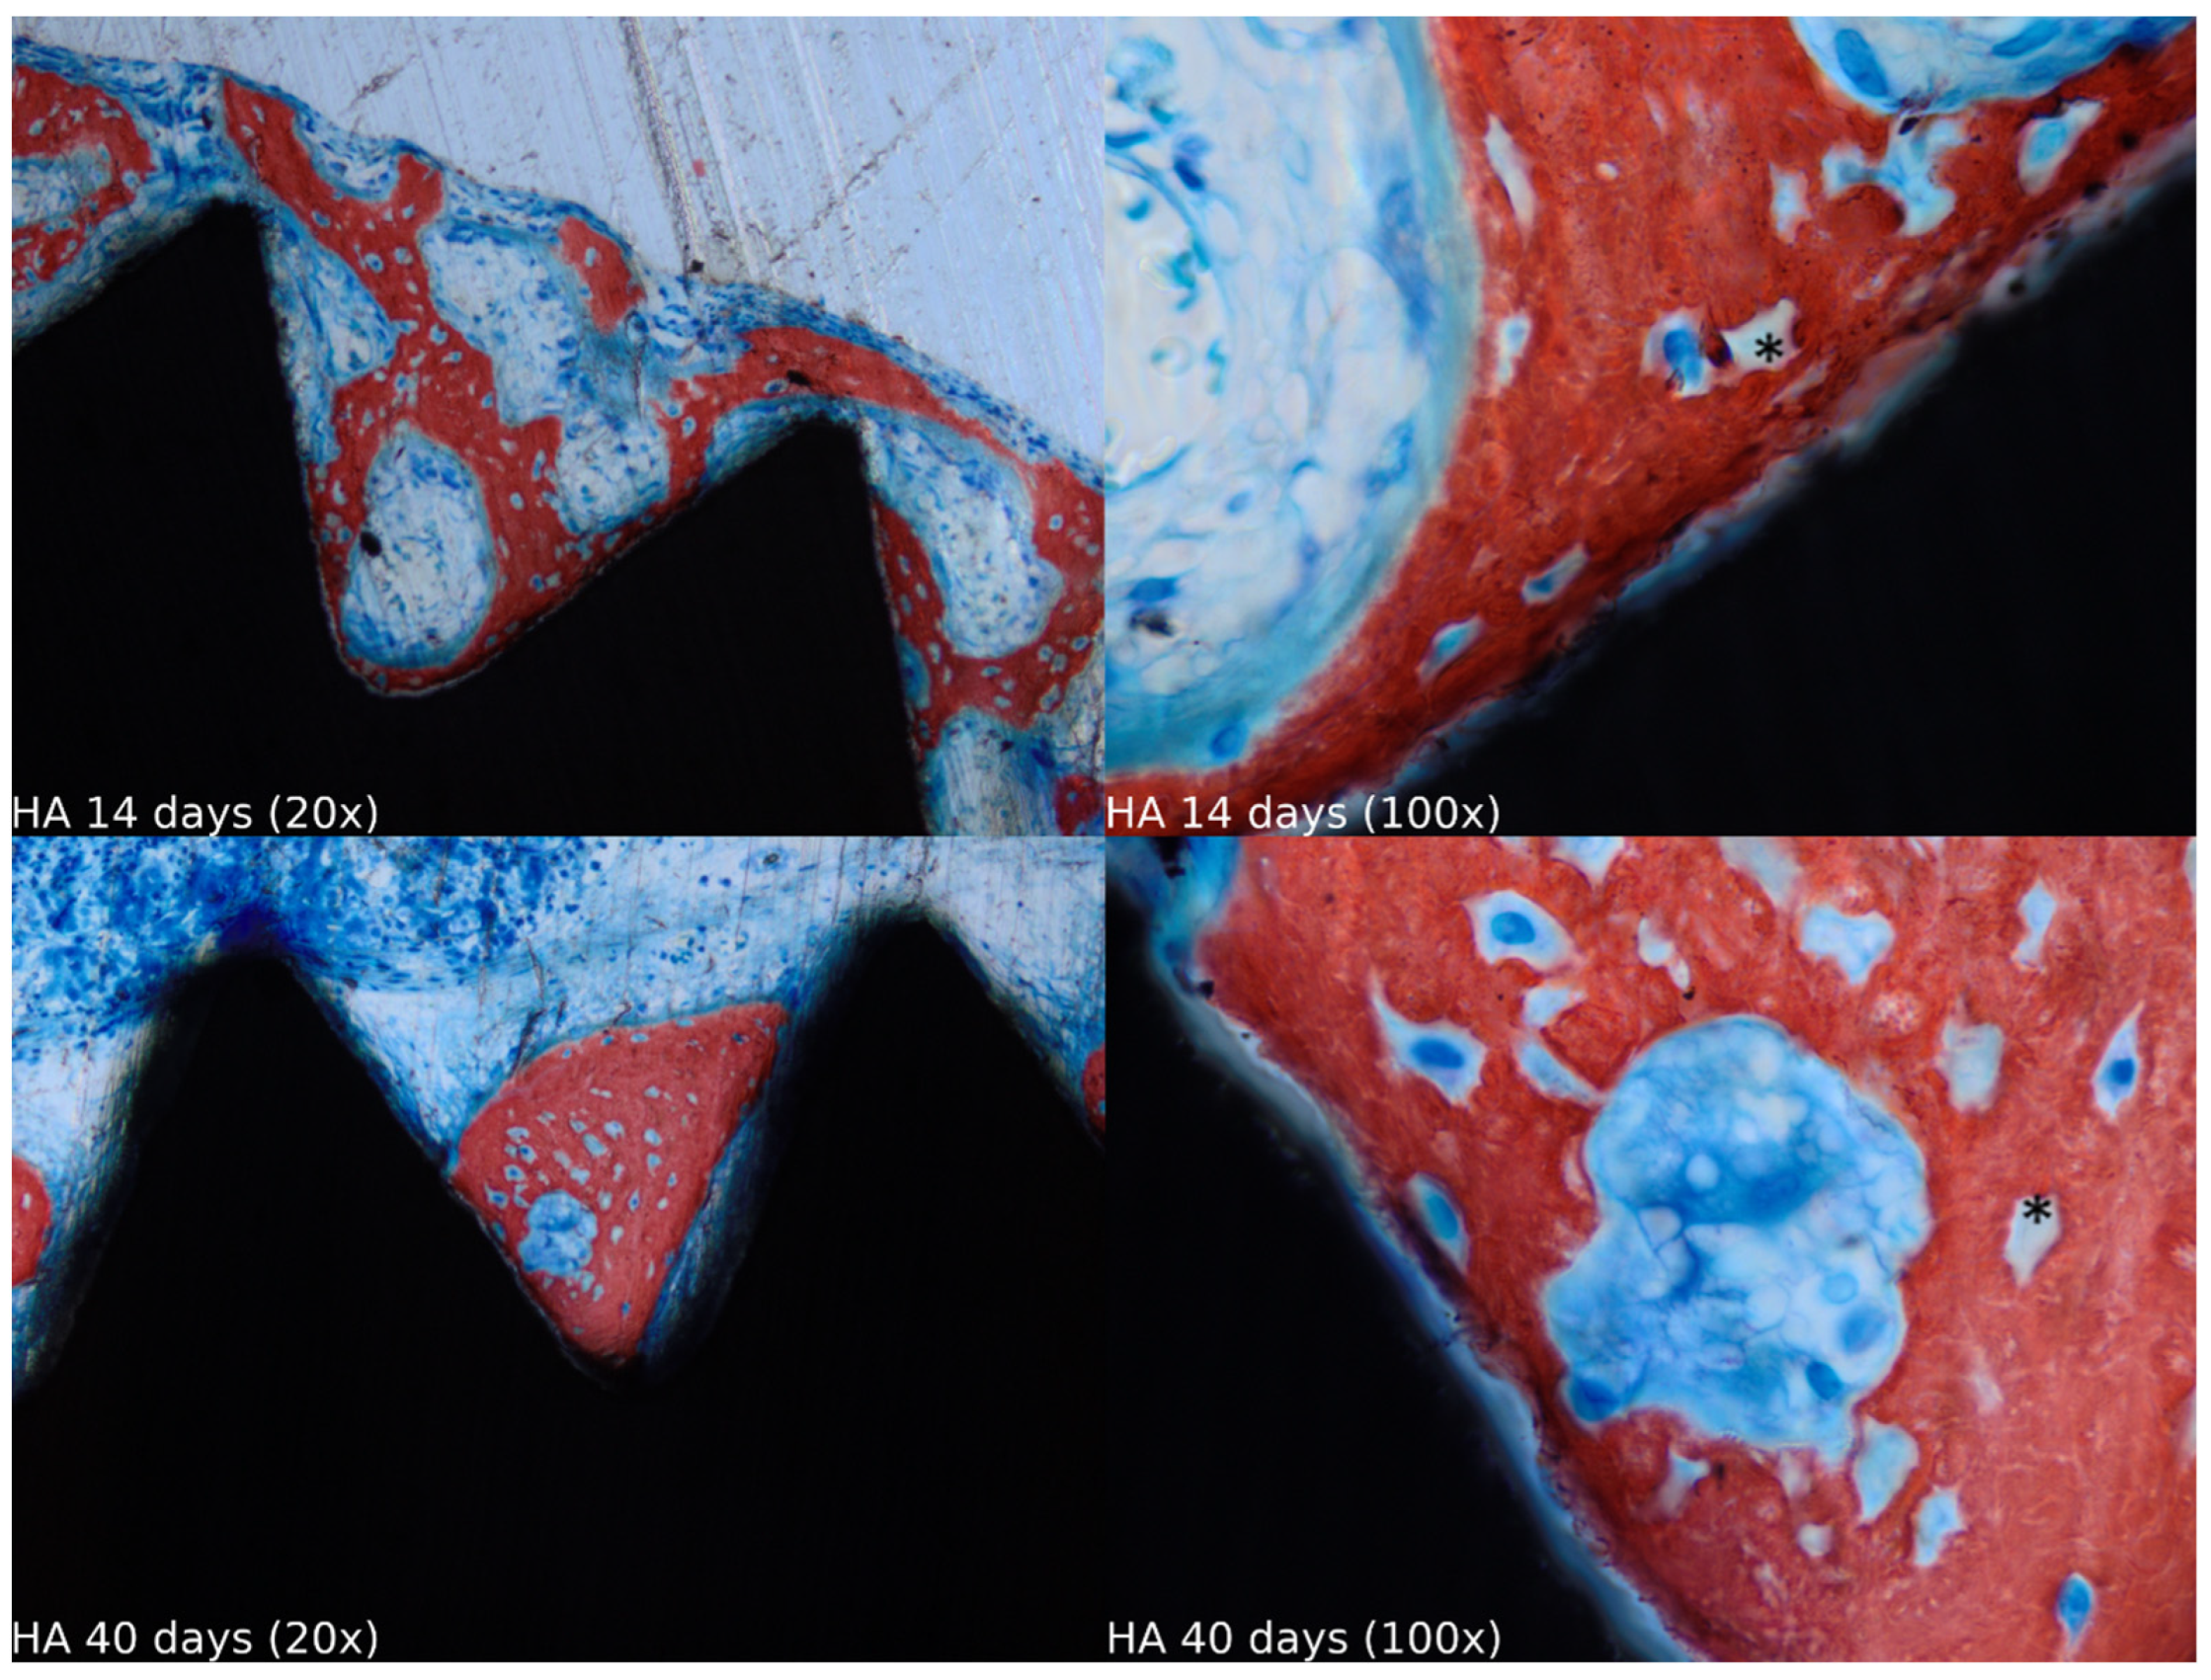

3.1. Descriptive Histology (n = 40)